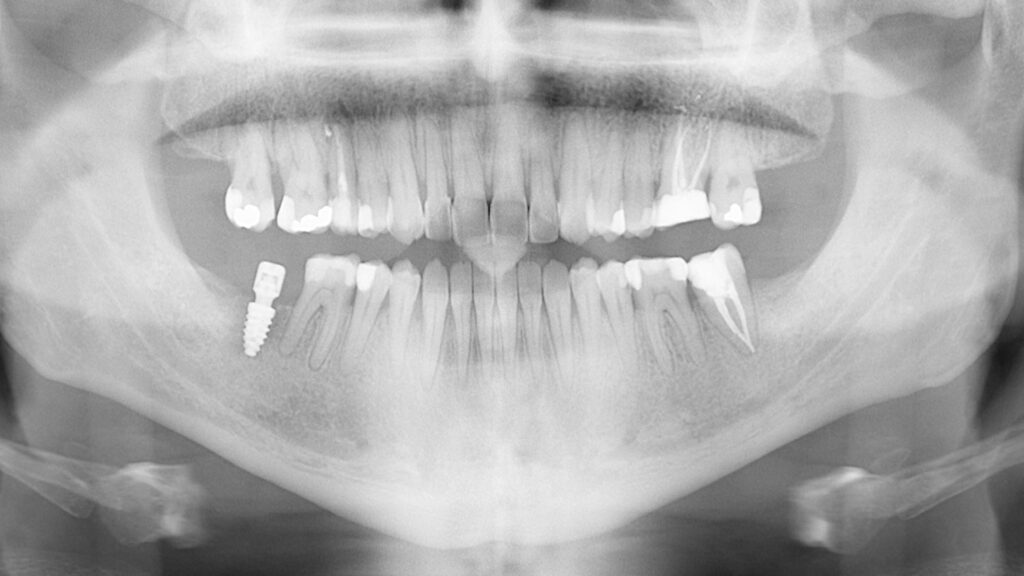

A 27-year-old male patient presented to the orthodontic practice after being referred by his general dentist. His primary concern was improving masticatory function. The patient had no notable medical history, nor had he received prior orthodontic treatment.

Extraoral analysis revealed a facial biotype consistent with a Class III malocclusion, maxillary compression, a gingival smile, mandibular asymmetry with deviation, and a dolichofacial pattern.

Intraoral examination showed an Angle Class III relationship on both sides, along with an anterior open bite. Additionally, a narrow maxilla with a bilateral posterior crossbite was observed.

The patient was informed of various treatment options, including combined orthognathic surgery and orthodontic appliances. However, he opted against surgery. Consequently, a compensatory orthodontic treatment plan using MARPE (Mini-Implant Assisted Rapid Palatal Expander) and Spark Aligners was chosen, after the extraction of the existing third molars and treatment of the cavities.

Ultimately, we successfully corrected the crossbite, open bite, and Class III canine relationship. The patient rehabilitated tooth #26 with an on lay and tooth #47 with an implant, resulting in a stable occlusion. Post-treatment retention involved a fixed retainer in the lower arch and removable retainers for both upper and lower arches to maintain the treatment results.